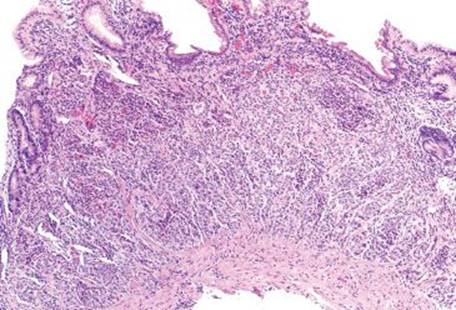

Figure 2.83 Chronic gastritis pattern, well-differentiated neuroendocrine (carcinoid) tumor (type I). Prolonged and unchecked gastrin stimulation of the ECL cells can lead to transformation of ECL cell hyperplasia into neuroendocrine tumors (type I, when in the setting of AMAG). One should always carefully evaluate of the background gastric mucosa in all cases of gastric neuroendocrine tumors to aid in classification, treatment, and prognosis.

Figure 2.84 Chronic gastritis pattern, well differentiated neuroendocrine (carcinoid) tumor (type I) (chromogranin immunostain). Previous case (Fig. 2.83). The distinction between reversible nodular ECL cell hyperplasia and neuroendocrine neoplasm is somewhat arbitrary. The College of American Pathologists suggests a size threshold of ≥0.5 mm for neuroendocrine tumors, whereas smaller nodules are considered ECL cell hyperplasia (or “dysplasia”).